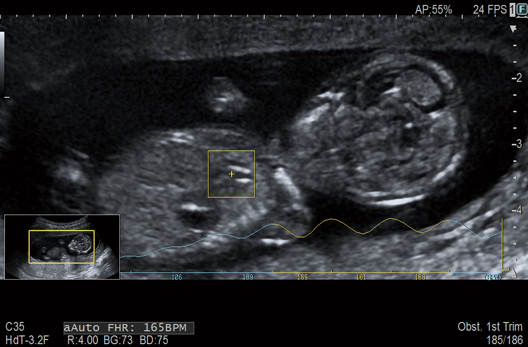

The fetal heart rate can be automatically calculated using a tracking ROI

placed over the fetal heart on the B mode image in real time. This offers a safer and more objective measurement compared to conventional Doppler or M-mode methods. Furthermore, as this function is also available on a transvaginal transducer, assessment can be made from early gestation onwards.